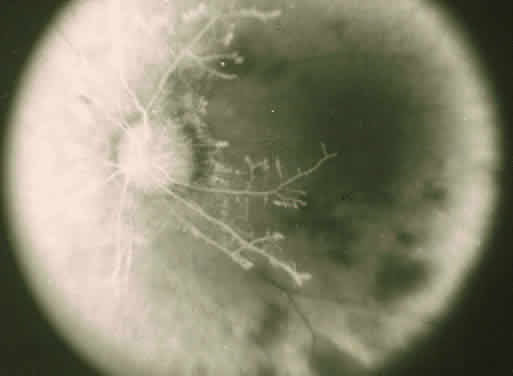

The ocular manifestations of antiphospholipid antibodies include retinal venous and arterial occlusions, amaurosis fugax, diplopia, and visual field loss.34,35 Extensive vasoocclusion, neovascularization, and vitreous hemorrhage may occur (Fig. 3). Treatment consists of photocoagulation for the neovascularization and systemic anticoagulation and immunosuppression. Vitrectomy may be required for vitreous hemorrhage. The role of systemic treatment of lupus anticoagulant in the management of ocular disease is unclear. Some investigators suggest that systemic anticoagulation be started promptly.36 The optimal duration of anticoagulation and whether antiplatelet therapy should be used are not known however. The optimal use of corticosteroids or other immunosuppressive drugs such as cyclophosphamide and azathioprine also is unknown. Two reports have found an association with the antiphospholipid syndrome and some additional retinal conditions. One report also has associated the primary antiphospholipid syndrome with central serous chorioretinopathy.37 In addition, lupus anticoagulant positivity could represent an additional risk factor for diabetic retinopathy according to a recent report.38